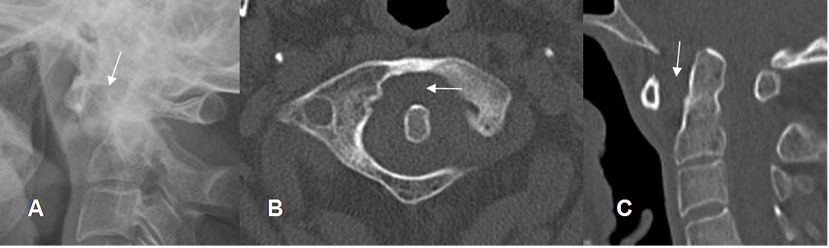

En la columna cervical, puede encontrarse erosión, subluxación de la articulación atlantoaxoidea o impactación y compromiso de las articulaciones interapofisiarias. (2).

En la subluxación hay laxitud del ligamento transverso, con aumento del espacio entre C1 y C2, en la proyección lateral en flexión. (2). (Fig 29 A y B).

Fig 29 A. Artropatía reumática.

A: Rx lateral, B: TAC axial y C: TAC reconstrucción sagital. Aumento del espacio atlantoaxial y sin antecedente de trauma, por laxitud ligamentaria.